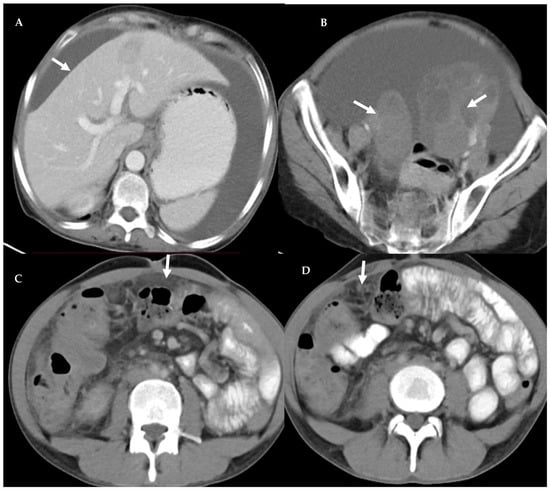

3.4. Peritoneal Involvement

3.5. Predictors of Peritoneal Carcinomatosis